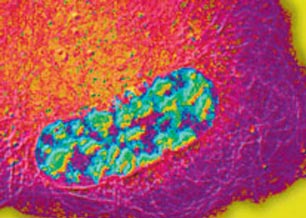

Breaks in one strand of DNA arise spontaneously every day from various sources including abortive activities of endogenous enzymes and reactive oxygen species produced during normal metabolic activities. These types of DNA breaks underlie the clinical utility of important classes of anti-cancer drugs and their progressive accumulation causes neurodegenration in humans. This is highlighted by defects in the 3’-DNA processing enzyme tyrosyl DNA phosphodiesterase (TDP1) which removes stalled topoisomerase 1 peptide from DNA termini. Despite this important catalytic function fulfilled by TDP1, it remains together with the newly identified enzyme TDP2 the only human enzymes that display this catalytic activity. Here, we employ a combination of yeast genetics, molecular, cellular, and whole animal approaches to understand the mechanisms of repair of this type of DNA break and determine their impact on neuronal viability and human health.